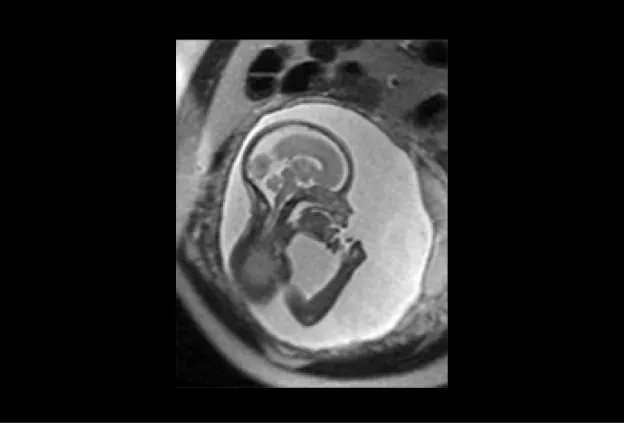

fetal mri baby scan

MRI image of a 30 week fetus shows normal fetal brain on this sagittal image (acquired in the midline of the brain). Notice how much detail can be seen of the foldings (sulci and gyro) of the brain, the brain stem, and the cerebellum.

UCSF is one of the few sites in the country that is experienced with performing and interpreting fetal MRI. We have performed fetal MRI since 1996. The findings from our fetal MRI study will help us provide pregnant women with the most advanced and accurate information during their pregnancy.

First, we would like to see how accurately fetal MRI detects changes in the fetus’ brain and spine during pregnancy compared to ultrasound.  While ultrasound is the most commonly used method of monitoring fetal development, its ability to detect changes in the brain is limited.  In this study, we are comparing ultrasound and MR images of fetuses to identify the situations in which fetal MRI will provide valuable clinical information not seen on ultrasound.  Studies have shown that, overall, fetal MRI is more helpful than ultrasound in evaluating the brain. We are interested in studying just how helpful fetal MRI is for different brain conditions.